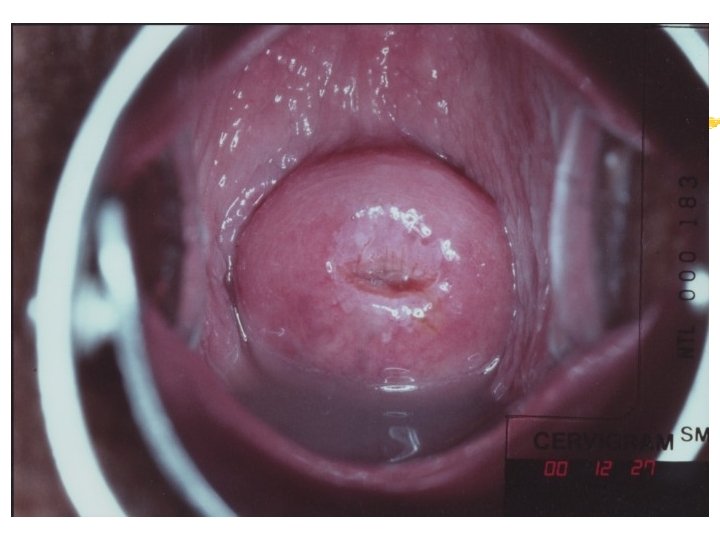

Warning signs of early cervical cancer 1. Yellowish and friable epithelium 2. Abnormal contour 3. Ulceration 4. Atypical vessels 5. Very severe colposcopic atypia 6. Large, significant lesion 7. Canal lesion, going out of range 8. Perimenopausal and post radiation

Atypical transformation zone 1. Acetowhite epithelium 2. Vascular structure a. Mosaic pattern b. Punctation c. Abnormal vessels 3. Leukoplakia

Acetowhiteness 1. SIL …dehydration of nuclear dense lesion 2. HPV …keratin swelling in HPV infected cells 3. Immature squamous metaplasia 4. Healing/regenerating epithelium 5. Congenital transformation zone 6. Inflammation 7. Adednocarcinomas Invasive squamous carcinoma

Cervicography: This is NOT Colposcopy High-quality colposcopic-type photography of the cervix Cervicoscope - Hand-held camera with a macrolens and a ring-flash Cervicogram - 35 -mm photo slide is taken Principles Recognition of lesions by means suitable magnification and illumination Fix up the problems of colposcopy 1. a less expensive form 2. noninvasive method 3. do not require expert skill

Procedures of cervicography A) Taking a 35 -mm cervicogram (1) Insert speculum and open as wide as possible … expose an entire cervix and upper vagina (2) Apply first application of 5% acetic acid by dabbing … cleanse the cervix of blood and mucus (3) View the cervix through the cervicoscope … allows time to begin taking epithelial change (4) Apply second application of acetic acid. (5) Take two cervicogram pictures B) Developing the images C) Interpreting a magnified image that was projected on the screen (1) Negative if no definitive lesions are visible (2) Atypical if there was evidence of acetowhite lesion of doubtful significance (3) Positive if there was evidence of a minor or major-grade lesion or cancer